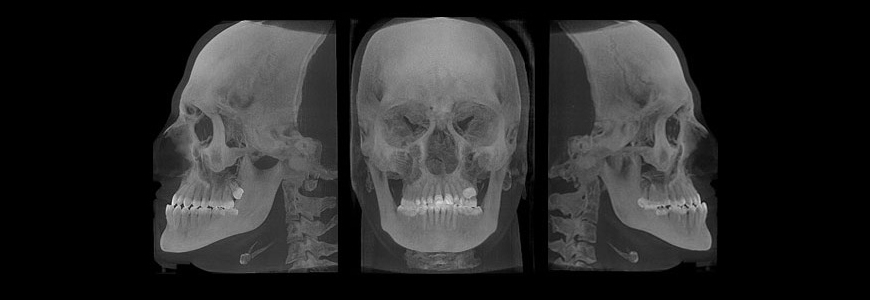

Es por ello que su análisis no solamente lo realiza viendo a su paciente sino que también requiere de ciertos estudios para confirmar el tipo de problema que tiene cada persona, profundizar sobre los tejidos, descartar presencia de quistes o tumores en los huesos, así como para establecer el plan de tratamiento que habrá de llevar a su paciente a una satisfacción de su tratamiento.

La importante necesidad de evaluar y revisar algunas radiografías de cara y cráneo, analizar una serie fotográfica clínica especial y analizar también unos moldes en yeso (replica de la boca del paciente en yeso), asegura un absoluto conocimiento del problema o de la serie de problemas que presente el paciente, tratando durante la terapia de corregir los problemas que más severidad se presenten en cada paciente.